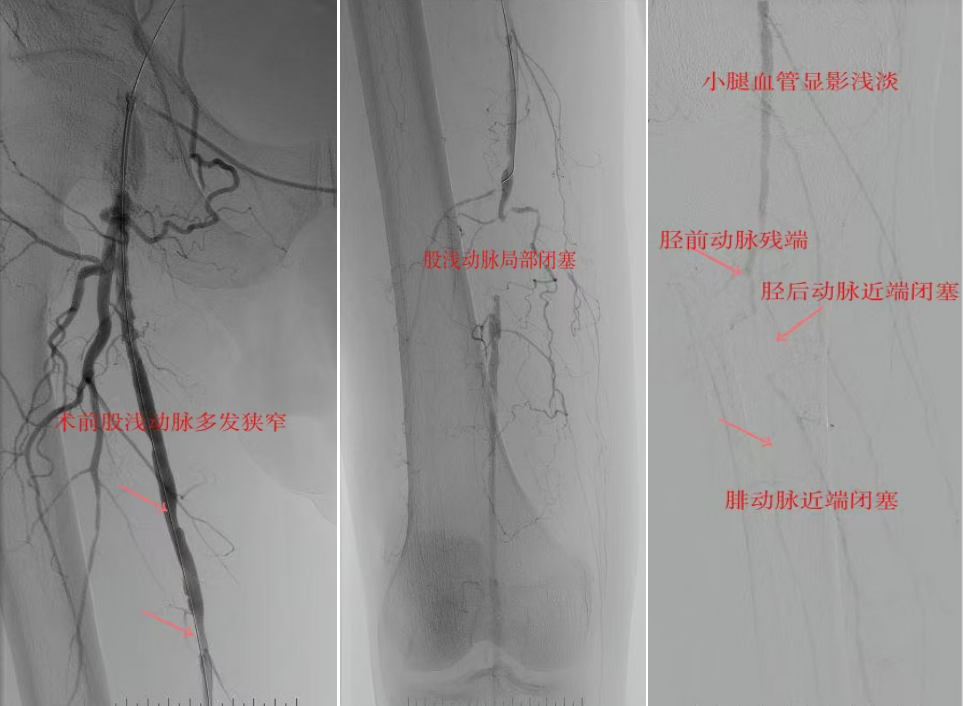

78岁男性患者,糖尿病合并高血压、脑梗塞,右足持续疼痛伴冰凉发绀3个月。入院CTA显示其右侧股浅动脉全程闭塞,膝下三支动脉均闭塞。医疗团队在局部麻醉下,再次巧妙应用“逆向开通技术”,经胫后动脉——足底弓逆向开通足背动脉及胫前动脉。术后患者右足皮温即刻回升,疼痛消失。术后结合中药外治(换药、熏洗、去腐生肌膏外敷)加速创面愈合,患者已顺利出院。

影像检查:CTA显示右侧股浅动脉全程闭塞,膝下三支动脉(胫前、胫后、腓动脉)完全闭塞。